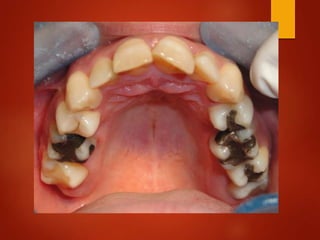

El documento es un registro médico odontológico que muestra las fechas de las visitas de un paciente al centro de salud El Raval, incluyendo exámenes y tratamientos realizados como la extracción de cálculos salivales en abril y mayo de 2012.